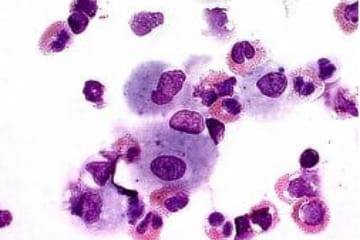

Eosinophilic Pneumonia

Sample from a patient with acute eosinophilic pneumonia (>40% eosinophils in the BAL, only two percent in blood). The eosinophils are bi-lobed with pink cytoplasm.